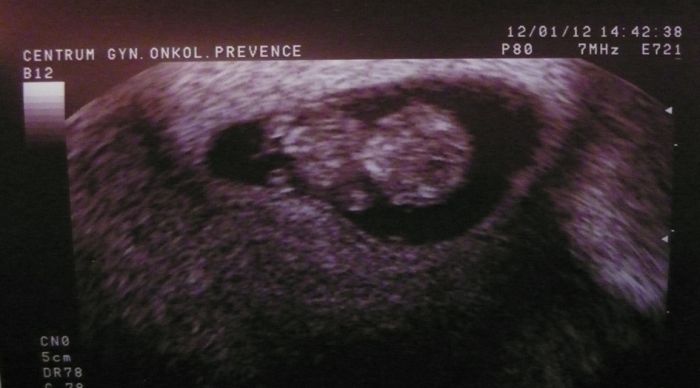

Ahoj holky...tak jsem byla dneska na tom vyšetřeí děložního čípku (kvůli dřívější konizaci) a poprosila jsem doktora, aby se podíval ma mimčo. Tak jsem viděla to mrskající se tělíčko, srdíčko bilo a odpovídá stáří podle početí ;-)

Ups...omylem jsem ho nahrála 2x, takže soráč :-)

[78481] Dělal mi to vnitřkem. Ale chvilku to trvalo, než našel polohu, kde je vidět jako člověk ;-) ...aby se dal udělat pěknej obrázek.